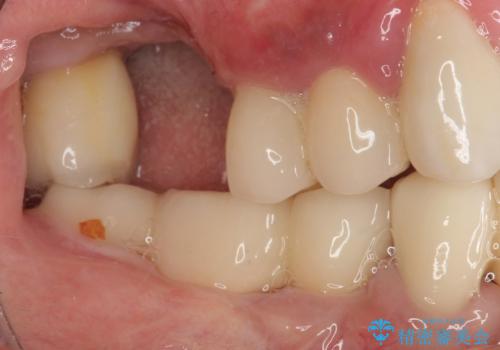

抜けてしまった奥歯 短期間インプラント治療

- インプラントが脱落してしまったとのことで来院された患者様です。

歯肉は綺麗に治癒しており、インプラント埋入に十分な骨があったため、速やかにインプラント埋入を行うこととしました。

インプラント埋入の状態が良ければ即日で仮歯を装着し、十分な生着が確認され次第、オールセラミッククラウンにて補綴治療を行うこととしました。

インプラントの初期固定も埋入後の生着もスムーズであったので、埋入から3ヶ月で無事に治療を終えることができました。